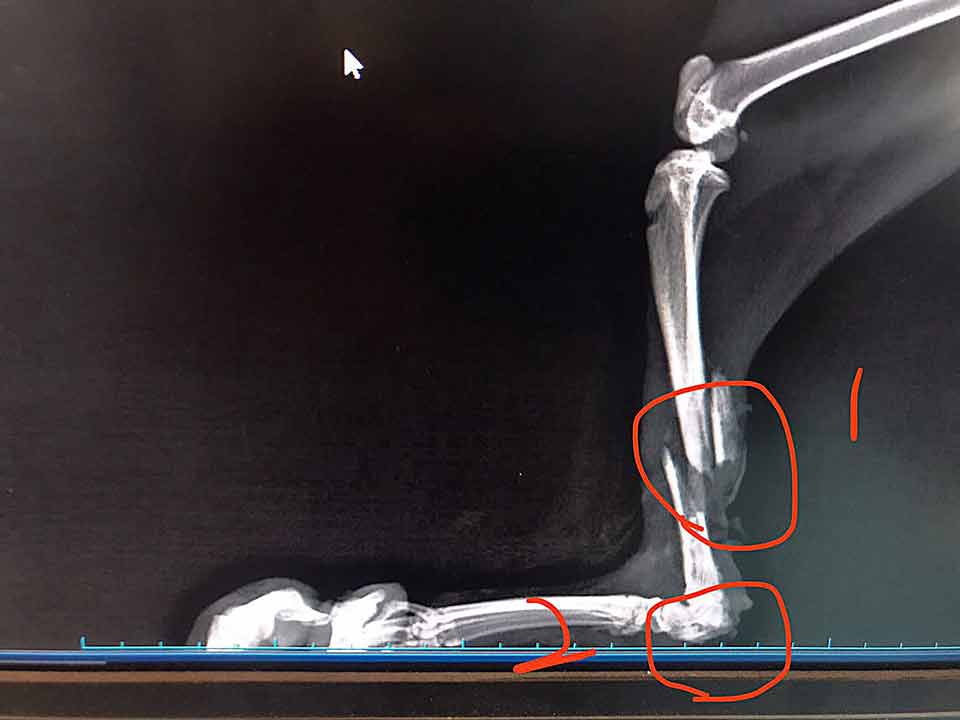

看著貓兒慵懶的模樣,可知他一個多月前,乾瘦無力,骨折、肌肉糜爛,卻被庸醫要求沒有經驗的救援人自行帶回照顧,等養胖一點再過來……!

貓兒雖然飢餓又重傷,卻超級親人!我們緊急送醫,打針吃藥、打骨釘、住院…… 一週後,愛生知道園區經濟拮据,認為我們有照護的能力,為了幫助節約,就讓我們帶回照顧了!

灰灰預訂七月初就可以拆除骨釘了,這個曾經一路坎坷的孩子,準備展開歡顏迎接新的《貓生》啦!